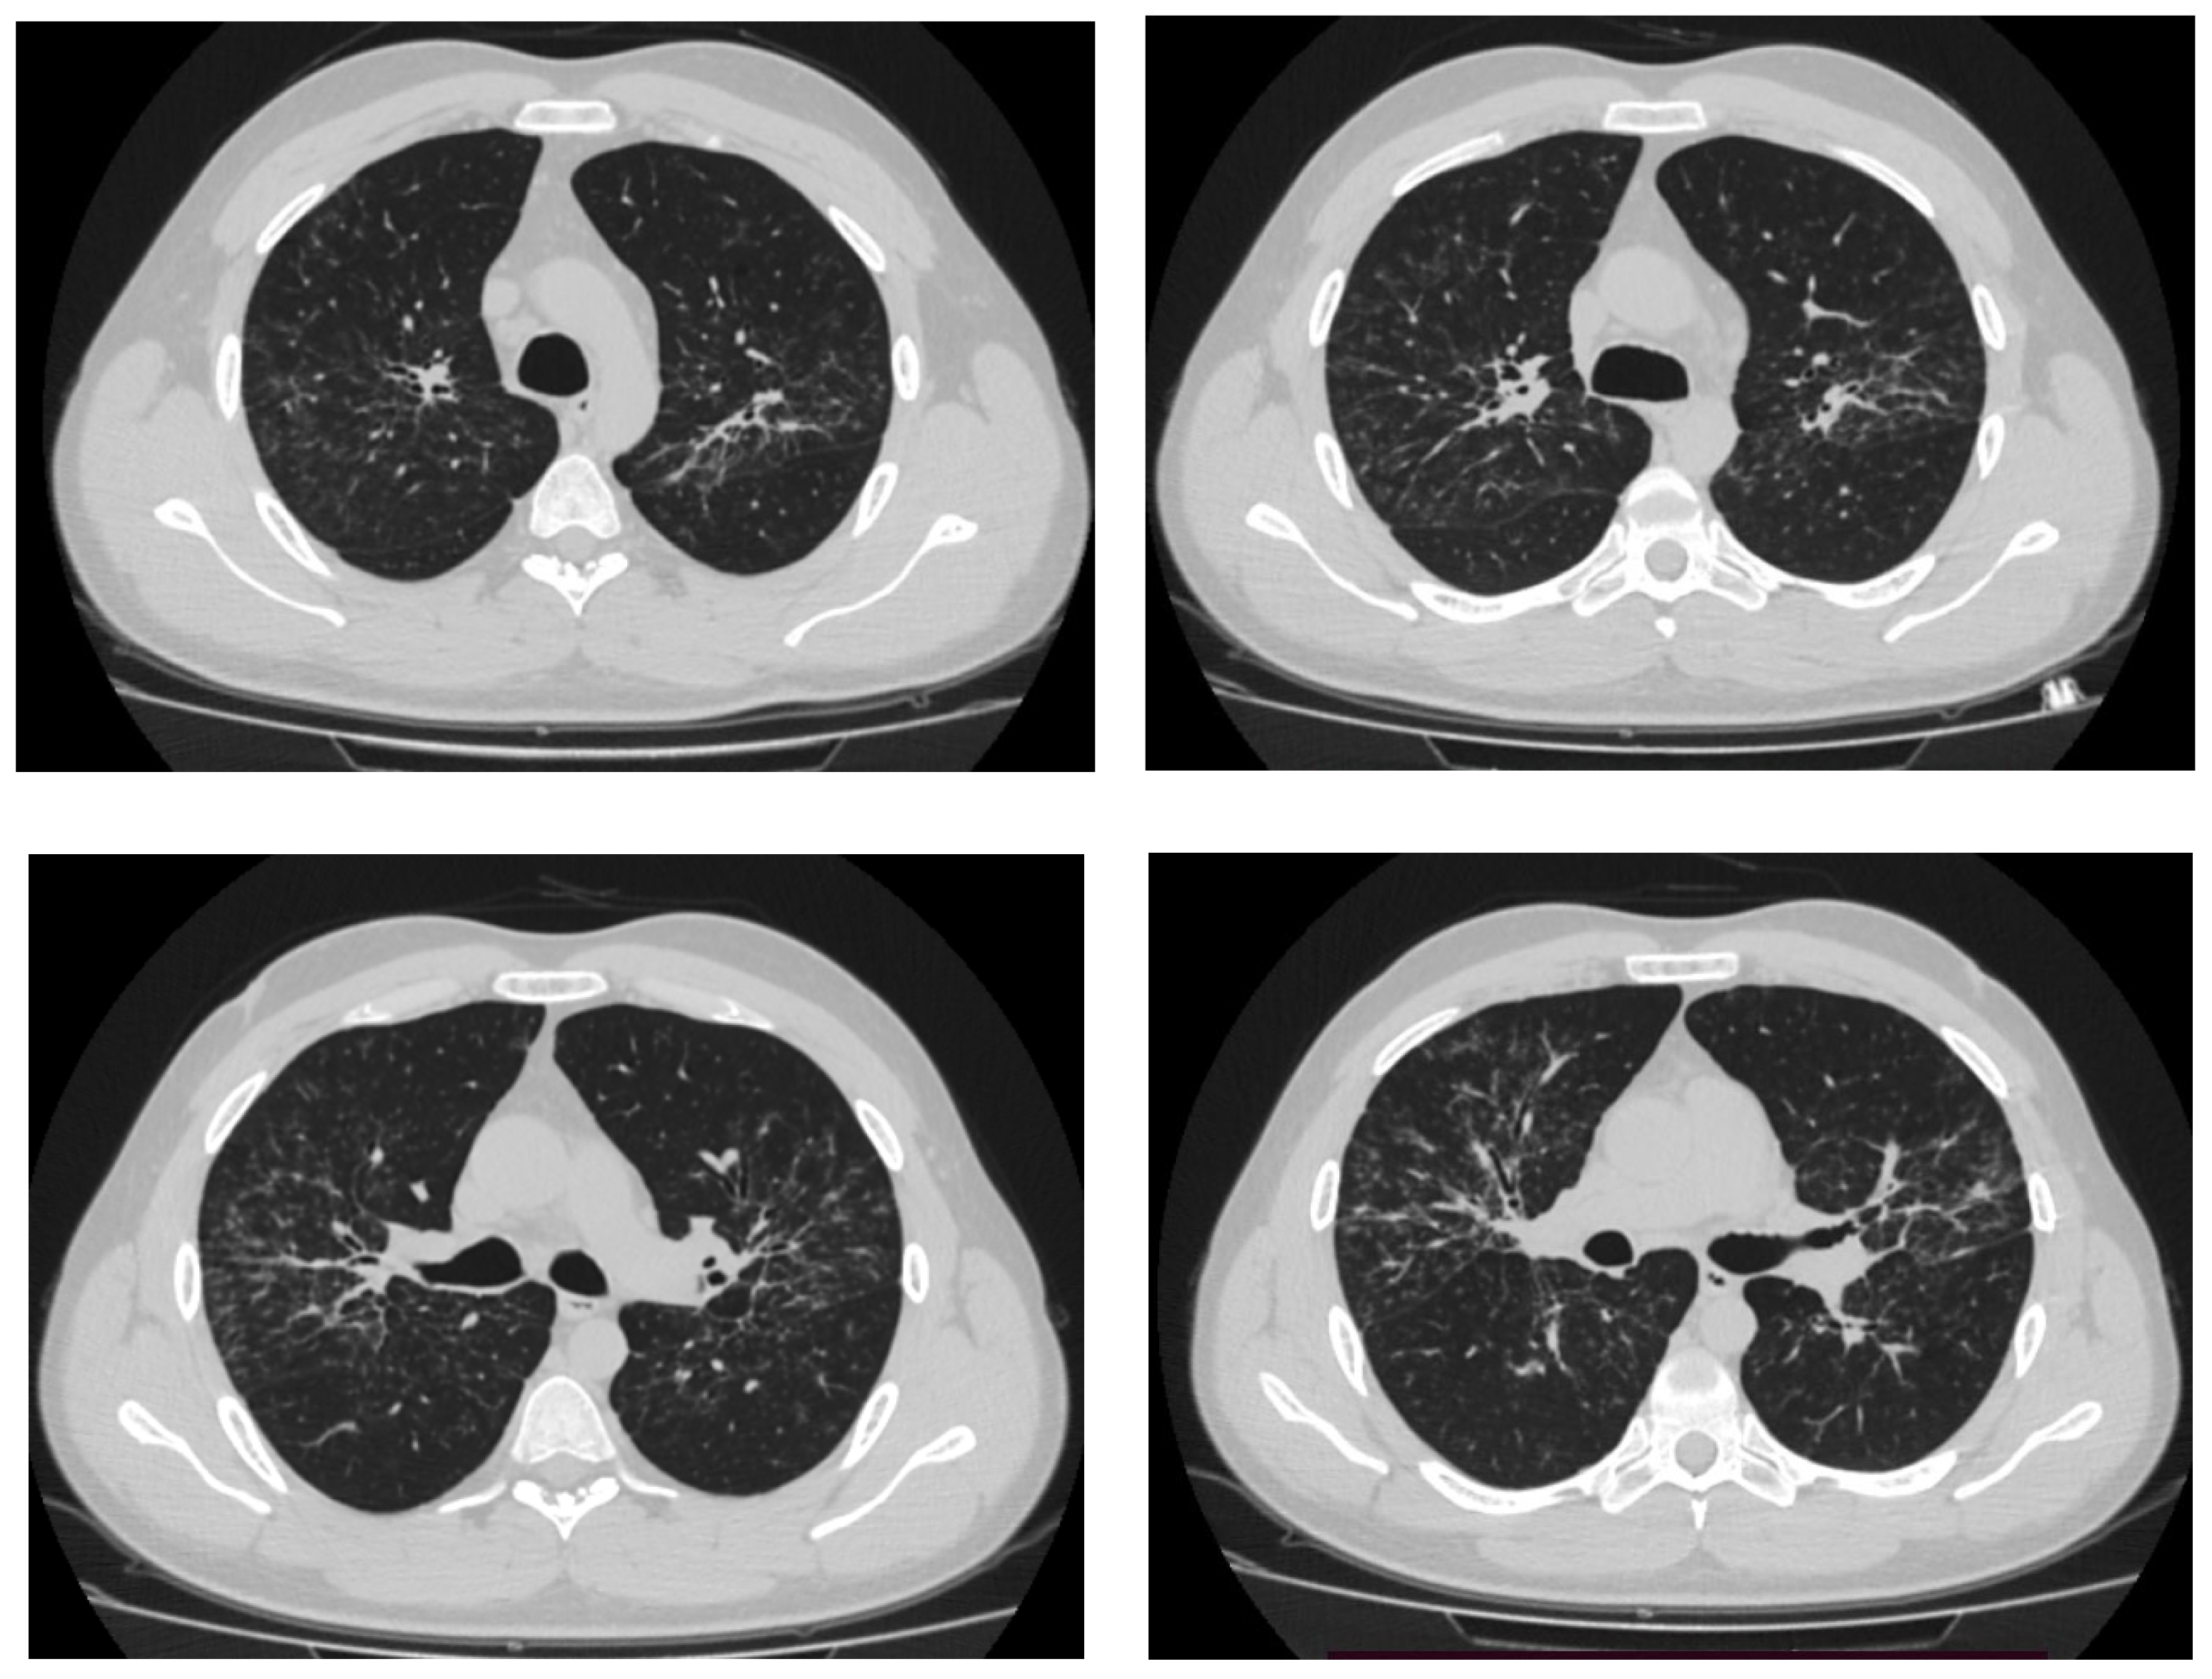

4. Different Manifestations and Causes of Pulmonary and Intrathoracic Lymph Node Sarcoidosis